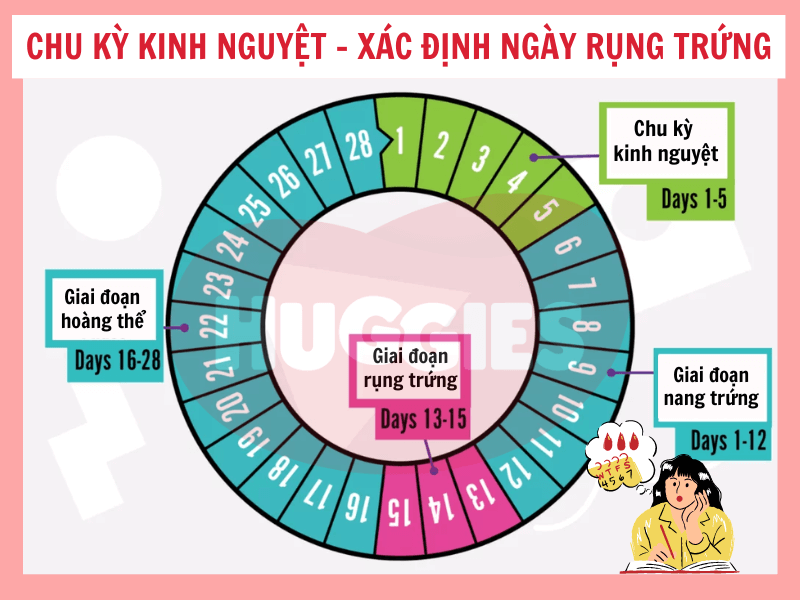

- Tin vào “tính ngày an toàn” nhưng chưa hiểu rõ cơ chế rụng trứng

- Tính ngày rụng trứng: Cần theo dõi chu kỳ kỹ lưỡng và không phù hợp với người có chu kỳ không đều.

Chào bạn thân mến, bạn có bao giờ tự hỏi làm thế nào để tính thời gian rụng trứng một cách chính xác nhất không? Việc hiểu rõ chu kỳ rụng trứng của bản thân không chỉ là kiến thức quan trọng về sức khỏe giới tính, mà còn là một cách tuyệt vời để […]

Chào bạn yêu quý, chúng ta lại gặp nhau rồi. Hôm nay, chúng ta sẽ cùng nhau trò chuyện về một chủ đề rất được quan tâm, đặc biệt là với những ai đang mong muốn chào đón một thành viên mới trong gia đình: đó là cách tính ngày rụng trứng thụ thai. Hiểu […]

Chào bạn thân mến, Tại Chuyenseg, chúng mình hiểu rằng hành trình khám phá và làm chủ cơ thể mình là một điều vô cùng thú vị và quan trọng. Đặc biệt, việc tính ngày rụng trứng chính xác là một trong những kiến thức nền tảng giúp bạn hiểu sâu hơn về chu kỳ […]